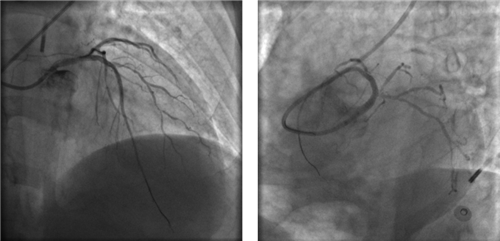

左主干完全閉塞

小心操作導絲及導管,艱難到達主動脈根部,但導管難以“到位”左冠口,“冒煙”見左主干居然完全閉塞了。

右冠近段嚴重狹窄,未見右向左的側枝循環(huán)

再行右冠造影,右冠近段也嚴重狹窄,未見右冠向左冠的側枝循環(huán)。

因患者股動脈扭曲,導管操控困難,術者反復嘗試,以導絲飄進左主干,在球囊的支撐下,通過閉塞段到達中間支,小壓力擴張后造影可見主干末端嚴重狹窄。隨后小心操控導絲到達回旋支、前降支,送入球囊擴張,嚴重狹窄的左主干末端被撐開,左冠血流終于恢復,胡女士暫時轉危為安。

球囊擴張后,左冠血流恢復,但左主干末端重度狹窄

左冠血流保持通暢

確認左冠血流保持通暢,大家懸著的心才稍稍放下。

根據IVUS檢查結果,在前降支近中段至左主干植入3枚支架,充分擴張后,狹窄完全解除,血流恢復通暢。

植入3枚支架,血流恢復通暢